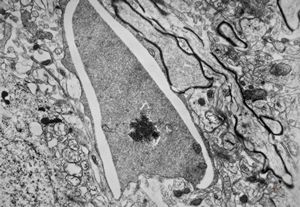

F,49y. | purulent meningitis- meningococcal v.s.

F,49y. | purulent meningitis- meningococcal v.s.

F,49y. | purulent meningitis- meningococcal v.s.